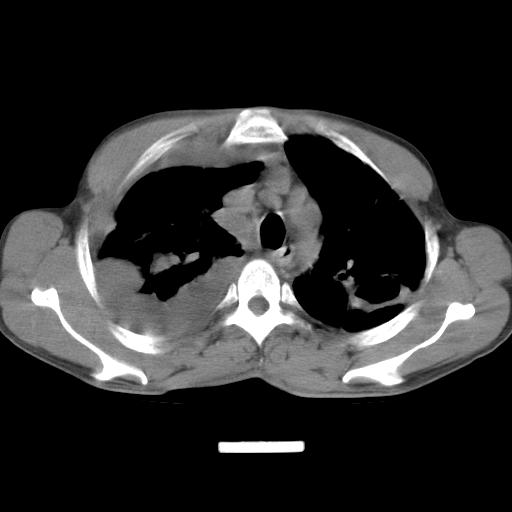

男性,44岁,结核病史多年。现胸闷气短,咳嗽,偶咳血。

1、右侧大量胸腔积液伴右肺压缩性膨胀不全,建议抽液治疗后复查 2、两肺继发性tb伴空洞形成。

1)两肺继发性肺结核伴空洞形成,左肺多发性结核球。2)右侧大量胸腔积液伴右肺部分膨胀不全。3)纵隔淋巴结肿大。

1,双肺多发结节 并空洞影改变, 左侧胸腔积液并部分包裹, 结合原病史首先考虑结核. 但也不除外其它.

2,左侧有一根肋骨陈旧性骨折? 建议追查 .

吉大一院胸水抽检结果:结核性胸水